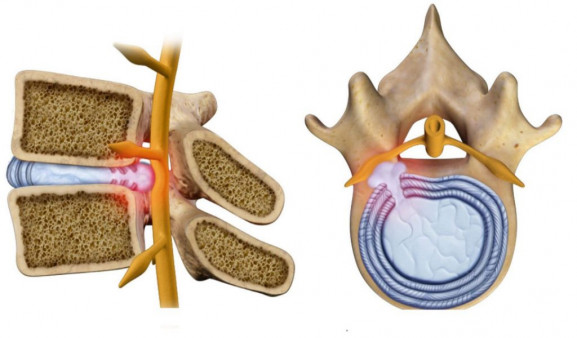

КТ-протрузии дисков: Визуализация и классификация